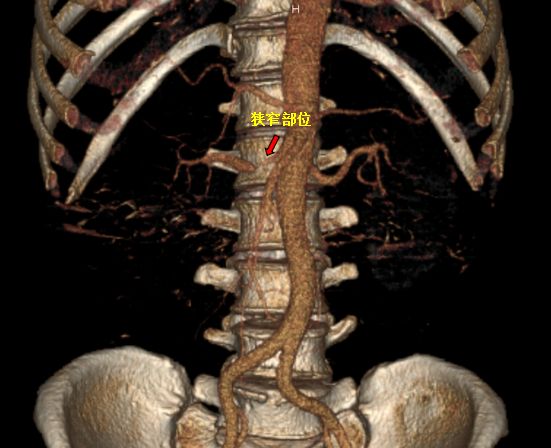

患者于4月9日上午送介入手术室行右肾动脉支架置入术。术中造影显示右肾动脉起始段明显狭窄,狭窄约90%,予置入肾动脉裸支架(7*19mm)后,造影显示右肾动脉狭窄解除,支架扩张良好,右肾灌注恢复。

a60c09d467d3b01e77d9133072a70a0.jpg

红色标记为支架置入后,狭窄解除